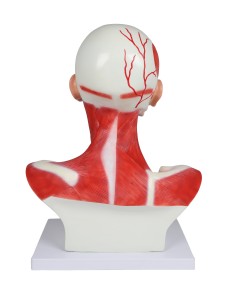

Dal cranio in 22 parti con incastri magnetici ai modelli di colonna vertebrale, da quelli di articolazioni a quelli di cuore, ogni pezzo della nostra collezione è progettato per un’immersione totale nello studio dell’anatomia umana. I nostri modelli, realizzati tramite scansioni di ossa vere, garantiscono un’esperienza tattile autentica e una fedeltà di peso quasi identica agli originali.

Essenziali per studenti e professionisti, i nostri modelli anatomici sono strumenti didattici che permettono di osservare le strutture anatomiche con precisione, eliminando la necessità di dissezioni o studi invasivi. Sono inoltre utili per spiegare ai pazienti le patologie, rendendo la comunicazione più efficace e risparmiando tempo prezioso.